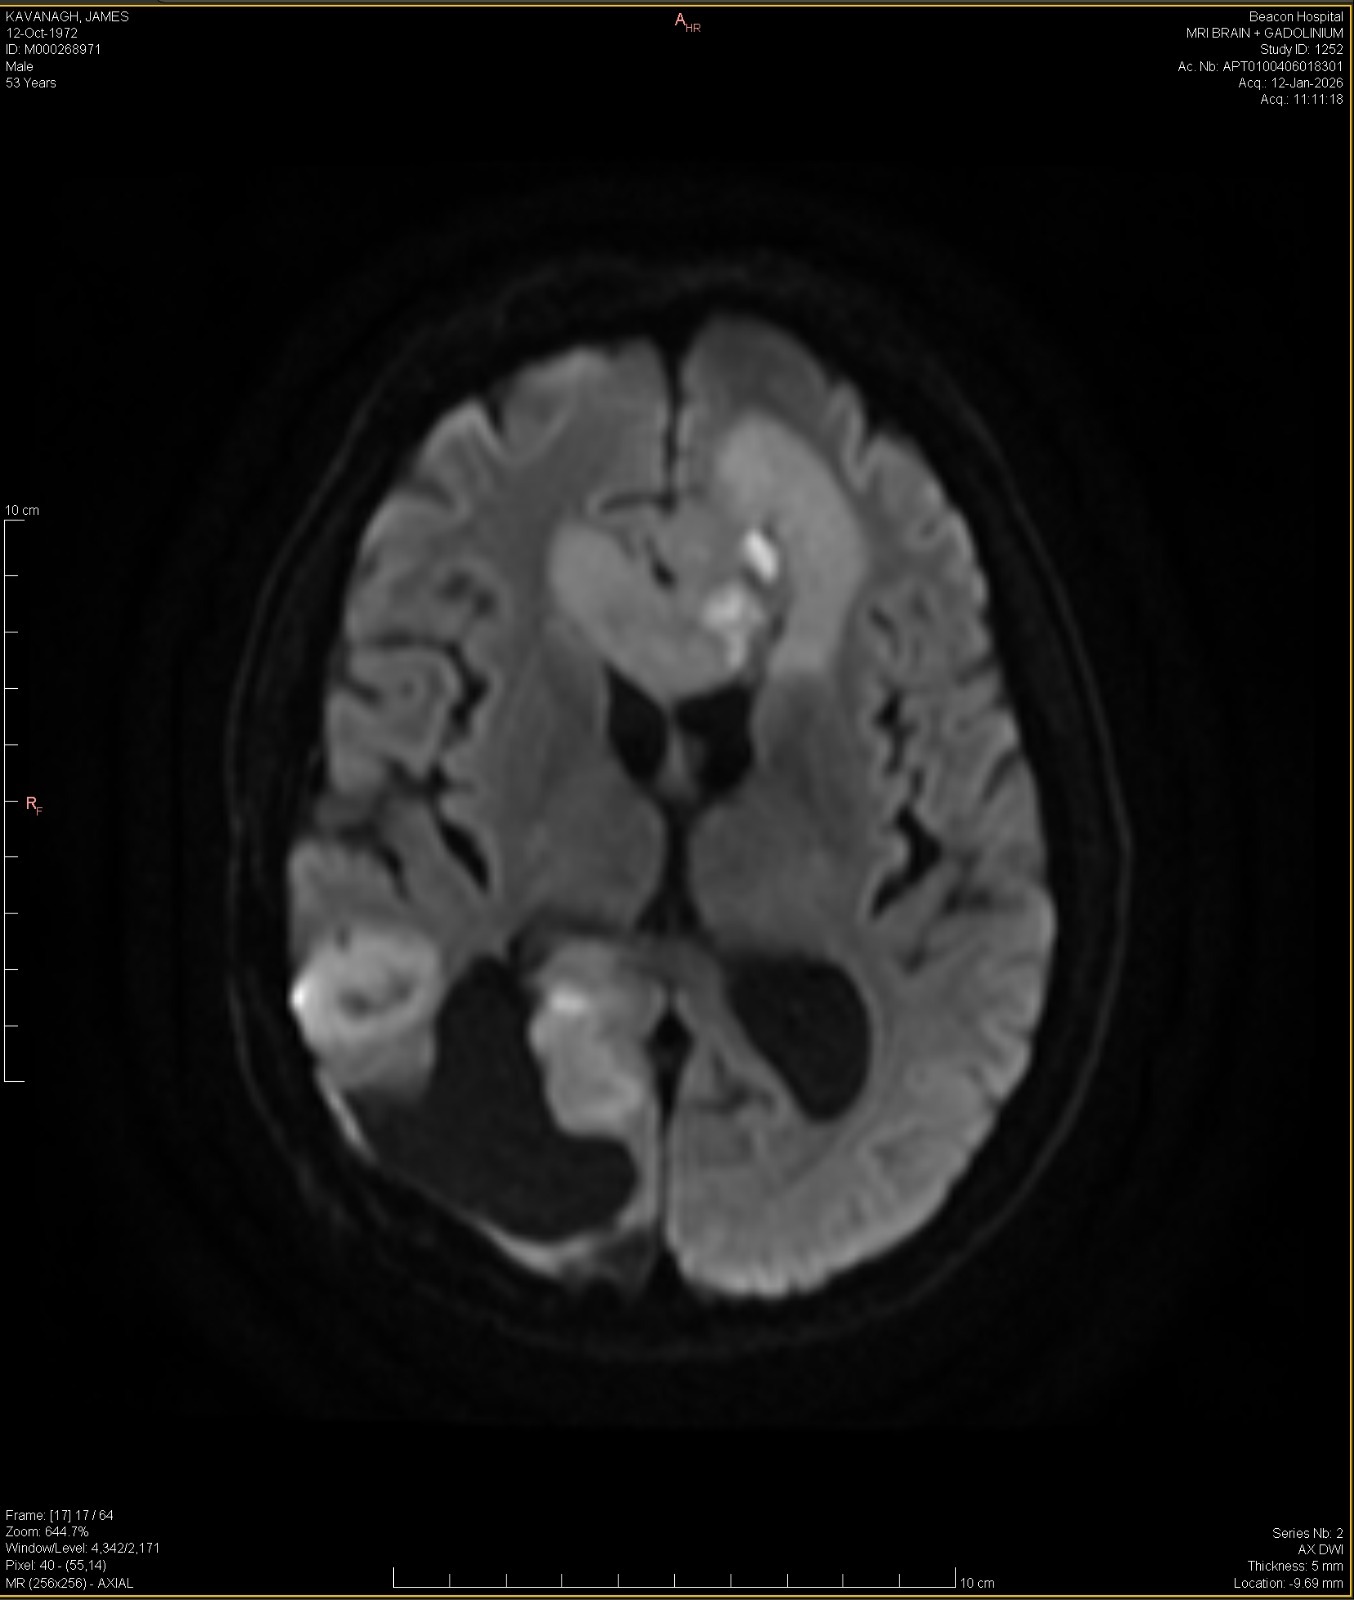

Our dear friend Jamie is facing the fight of his life. He has been diagnosed with stage 4 glioblastoma — an aggressive and life-threatening brain cancer. Despite the devastating diagnosis, Jamie has shown incredible courage and determination. He has already undergone two major brain surgeries to remove tumors, but the battle is far from over.

GLIOBLASTOMA MULTIFORME